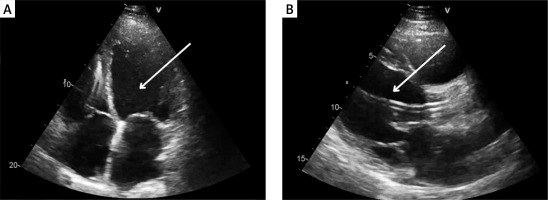

A 51-year-old male with a history of dilated cardiomyopathy, atrial fibrillation, diabetes and cardiac resynchronization therapy was admitted to the cardiology department due to another episode of decompensation of heart failure (HF). On admission, physical examination revealed peripheral oedema and abdominal pain. Blood investigations showed elevated N-terminal pro-B-type natriuretic peptide (NT-proBNP) at 4333 pg/ml (norm 0–125 pg/ml). Echocardiography disclosed enlargement of all heart chambers, moderate mitral regurgitation and reduced left ventricular ejection fraction of 19% (Figure 1 A). Despite the standard HF treatment with loop diuretics, deterioration was observed with hypotension and an elevated lactate level of 4.1 mmol/l. The severity of cardiogenic shock was assessed as stage D in the Society for Cardiovascular Angiography and Intervention (SCAI) classification [1]. The patient required infusion of dobutamine and levosimendan. Persistent abdominal pain and increased aspartate transaminase (AST) at 198 U/l (norm < 35 U/l) and alanine transaminase (ALT) at 213 U/l (norm < 45 U/l), prompted a computed tomography scan revealing potential indicators of cholecystitis, which were subsequently confirmed through ultrasonography. The Heart Team (HT) decided on an urgent implantation of an Impella CP device, followed by a cholecystectomy, and subsequent qualification for long-term left ventricular assist device (LVAD) implantation. Impella CP was successfully implanted through the femoral artery. Four days later, an open cholecystectomy with a right subcostal Kocher incision was successfully performed. There was no necessity to modify the standard operation protocol. During the procedure, the patient was supported with dobutamine, noradrenaline and Impella CP set to P5 level. Postoperatively, inotropic agents were progressively reduced until complete discontinuation. Initially anticoagulation was conducted using unfractionated heparin under activated clotting time (ACT), however heparin-induced thrombocytopenia was detected. Heparin was subsequently switched to fondaparinux. The patient was reevaluated by the HT and qualified for LVAD therapy. Eight days after the cholecystectomy, the Impella CP was removed and a HeartMate 3 LVAD was implanted. The patient was discharged 14 days later. This case highlights the critical role of the Impella CP device in initial hemodynamic stabilization and possibility to provide temporary mechanical circulatory support (tMCS) during urgent surgical interventions, as demonstrated by Anderson et al. [2]. Furthermore, it underscores the importance of tMCS in managing cardiogenic shock prior to destination therapy such as LVAD therapy.